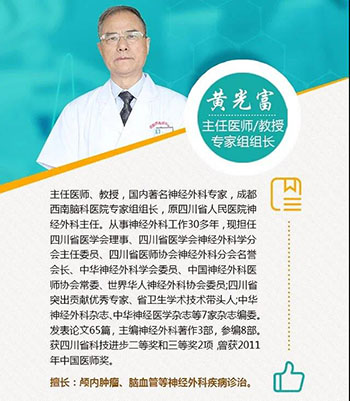

晏女士在医生的建议下,转入我院寻求黄光富教授的治疗。经检查,发现她左侧眼睑下垂,不能自己睁开。扒开眼皮,左瞳孔放大,对光反射消失,眼球偏外,且不能正常转动。头颅MRA检查后,确诊为左侧颈内动脉后交通段动脉瘤,拟行动脉瘤夹闭手术。